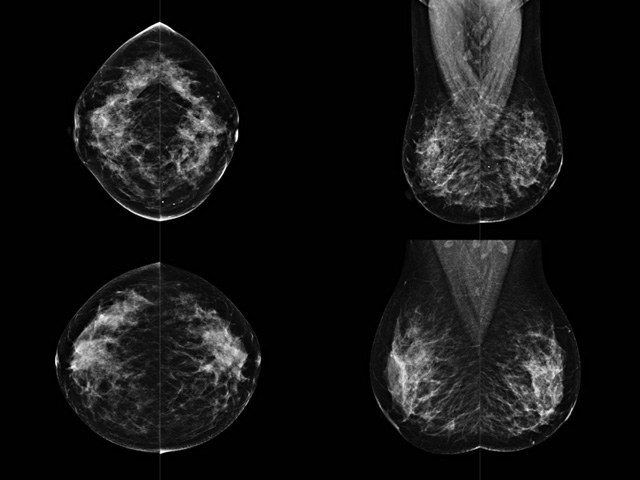

乳腺DR成像設備中非晶硅跟非晶硒兩種平板探測器。更要提供優(yōu)質的圖像質量乳腺的組織結構與厚度各不相同,減少重拍率輻射劑量,,乳腺的主要構成組織均為軟組織結構,組織之間密度十分相似,缺乏天然對比度。選擇軟X線攝影技術獲得良好對比度的乳腺結構影像。增加各組織對X線的吸收差異。乳腺攝影測和分類,平板探測器的像素尺寸范圍應在50到100μm之間。特別是微鈣化灶可以小到100到200μm,平板探測器都必極小微鈣化灶進行成像。

乳腺DR是利用X光來做檢查,在一瞬間將被檢測到的位置投影出來,因為是瞬間的輻射,所以只需要0.5秒的時間。因此對病人的輻射很低,大約是0.023mSv,比國家的標準要低得多。DR系統(tǒng)由 X線、發(fā)生裝置、直接轉換平板探測器、系統(tǒng)控制器、影像監(jiān)視器、影像處理工作站等組成。能檢查胸腔積液、肺結核、大葉性肺炎、肋骨骨折等。心室增大、主動脈擴張、主動脈瘤等心臟病。腹部病變,如腸梗阻、腸穿孔等,DR上可見液氣平面、膈下游離氣腫。DR表現(xiàn)不正常,要結合臨床表現(xiàn)、體征、癥狀等綜合分析,結合CT、彩超、血液分析等,才能作出正確的判斷。